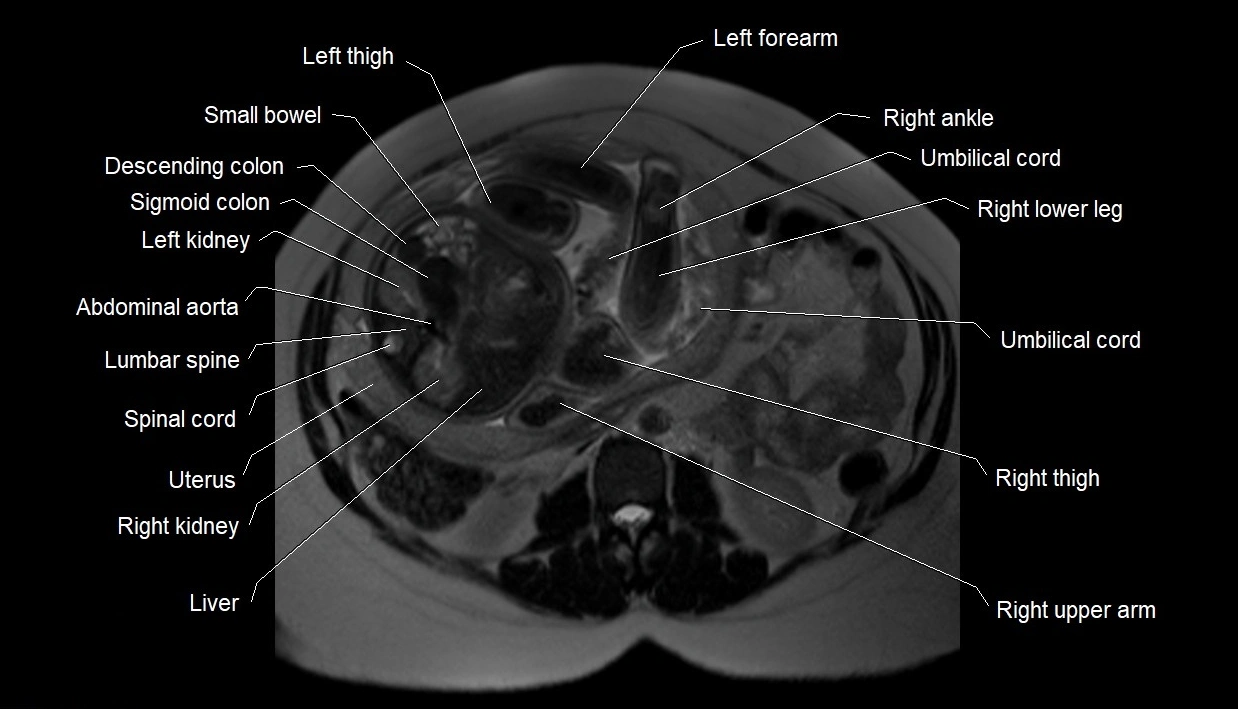

Relations

• Enclosed within the amniotic sac, bounded by the amnion and chorion

• Surrounds and cushions the developing fetus

• In continuity with maternal circulation through placental and transmembrane exchanges

• Imaging relevance: MRI used for fetal visualization and assessing oligohydramnios/polyhydramnios when ultrasound is inconclusive

MRI image

image